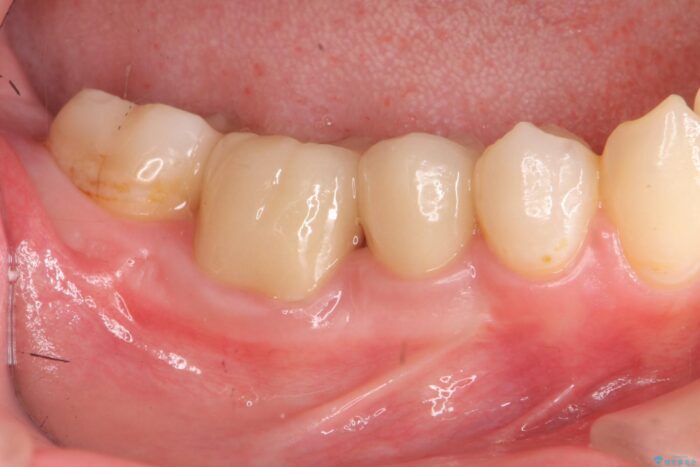

治療後について

歯ぐきの炎症も治まり、疼きなどの違和感もなくなりました。